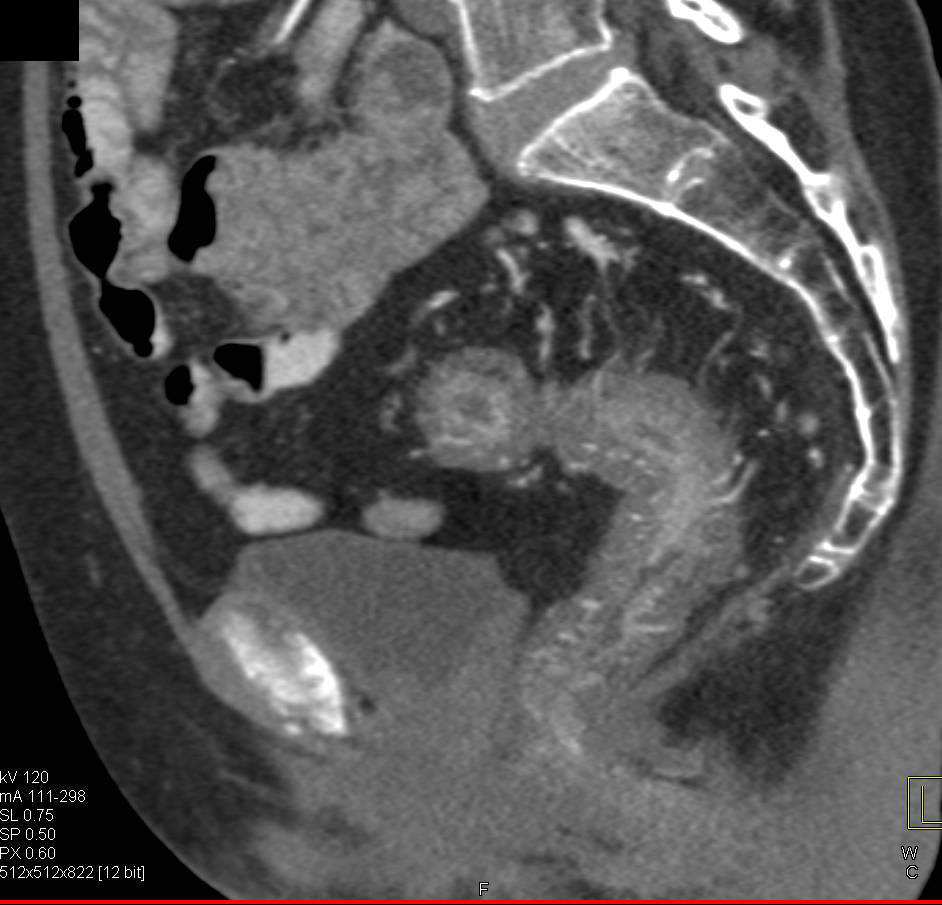

Pelvic Adenocarcinoma Adjacent to the Sigmoid Colon